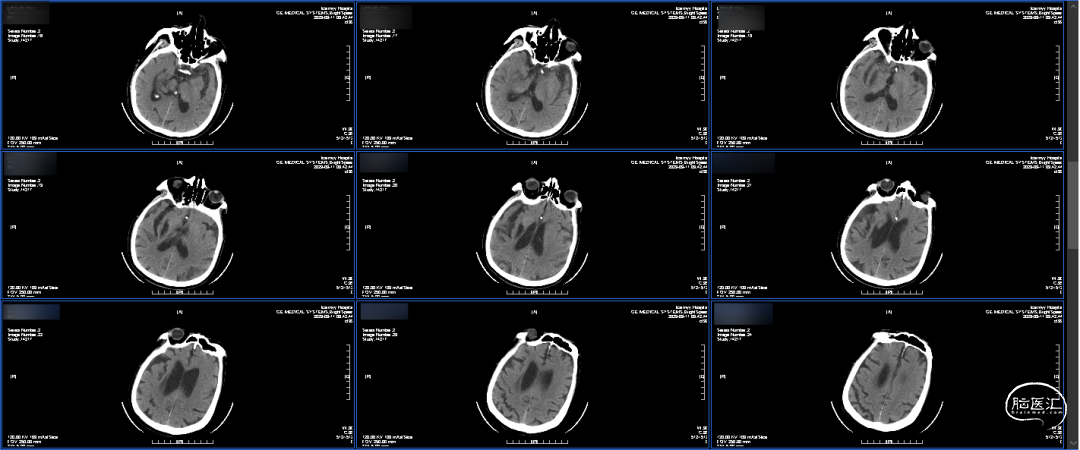

术后即刻CT:大脑纵裂高密度影,考虑出血(大脑前动脉超选困难,导丝损伤可能)。

术后第一天CT:血肿明显吸收减少。

出院前CT:出血完全吸收,左侧大脑半球未见确切梗塞灶。